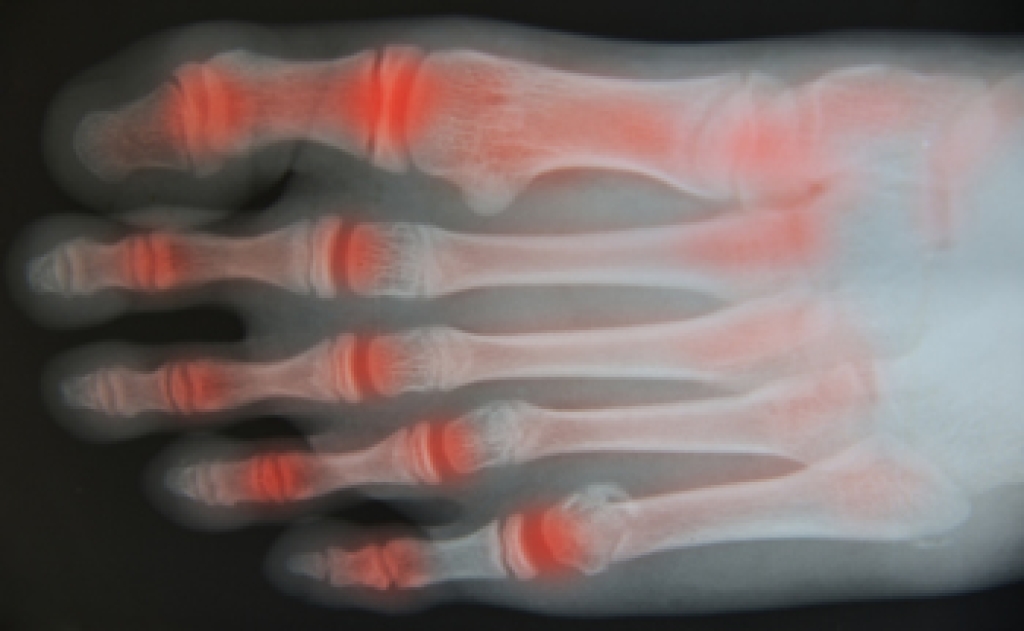

Foot arthritis is a condition where the joints in the foot become inflamed, leading to stiffness, swelling, and pain. It may result from wear and tear, autoimmune diseases, or injury. Flare-ups can be triggered by overexertion, stress, infection, or changes in activity, often causing increased joint pain and reduced mobility. These episodes may disrupt daily life and make walking or standing uncomfortable. A podiatrist can help manage symptoms through customized treatment plans, supportive footwear, orthotics, and lifestyle guidance. If you are experiencing ongoing joint pain in your feet, it is suggested that you consult a podiatrist who can provide effective relief and management techniques.

Arthritis is a joint disorder that involves the inflammation of different joints in your body, such as those in your feet. Arthritis is often caused by a degenerative joint disease and causes mild to severe pain in all affected areas. In addition to this, swelling and stiffness in the affected joints can also be a common symptom of arthritis.